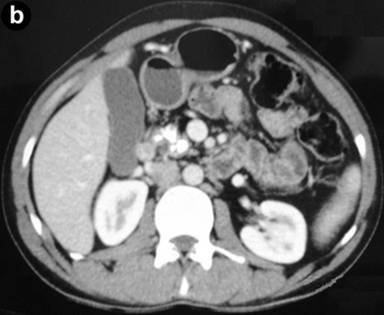

A 35-year-old male suffered from colicky abdominal pain in the right hypochondrium and epigastrium of four months duration, not associated with jaundice or weight loss. On admission, his total bilirubin was 0.7 mg/dL, AST 23 IU/L, ALT 15 IU/L, alkaline phosphatase 104 IU/L, GGT 9 IU/L and amylase 112 IU/L (reference ranges: 0-110 IU/L). A CT scan showed atrophy of the pancreas with a 1 cm dilatation of the pancreatic duct (Figure 3a). A calculus was seen in the pancreatic duct near the ampulla (Figure 3b). Diffuse dilatation of the common hepatic duct and the common bile duct was seen without any calculus, suggestive of a choledochal cyst. MRCP confirmed this finding and also showed significant atrophy of the pancreas; a pancreatic duct 1 cm in diameter (Figure 4) and an isointense filling defect was seen in the pancreatic duct at its distal end near the ampulla. A diagnosis of chronic calcific pancreatitis with type I choledochal cyst was made. He underwent choledochal cyst excision with a cholecystectomy, hepaticojejunostomy (end-to-side) and side-to-side pancreaticojejunostomy. Tissue from the head of the pancreas confirmed the diagnosis of chronic pancreatitis. Surgery and recovery were uneventful. He is asymptomatic after a 4 month follow-up.

Figure 4. MRCP showing a type Ic choledochal cyst with a dilated pancreatic duct and filling defect seen proximal to the ampulla (arrow). |